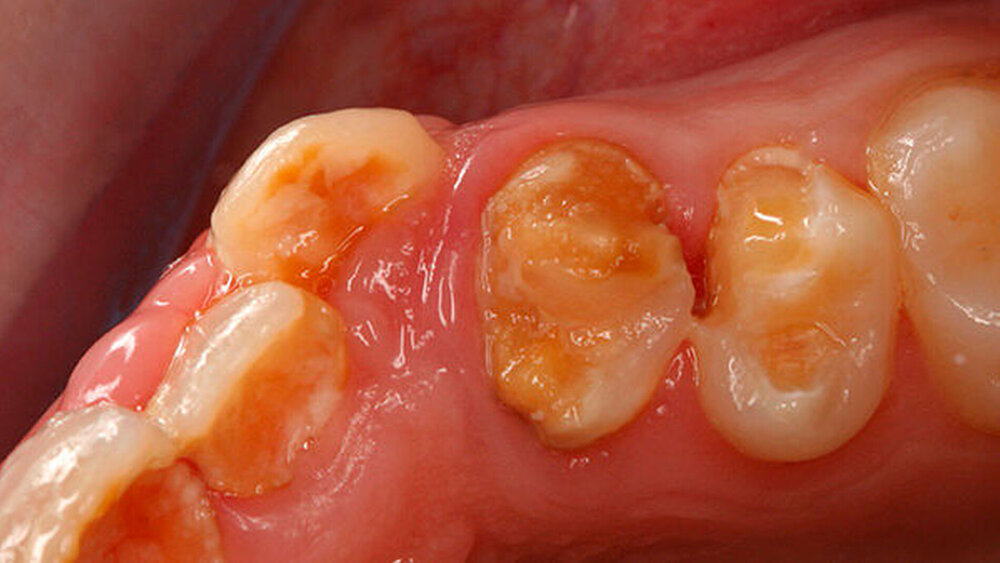

Abbildung 1 gibt einen guten Überblick darüber, dass teils mehrere Restaurationen pro Zahn durchgeführt wurden und die dazwischen verbliebenen Bereiche aus Zahnschmelz oft nur gering waren (insbesondere an den Frontzähnen). Gleichzeitig zeigt aber auch der Vergleich der kontralateralen Prämolaren, wie anfällig dieser verbliebene Schmelz für Abplatzungen war. Im Unterkiefer ist gerade an Zahn 37 deutlich zu erkennen, wie großflächig die Schmelzverluste sein können, wenn auch die Restauration nicht mehr intakt oder vorhanden ist.

a) Dentinogenesis imperfecta. Da alle Zähne betroffen sind, ist von einer genetisch bedingten Fehlbildung auszugehen. Die Zähne der Patientin weisen zudem eine veränderte Farbe auf. Darüber hinaus sind Abplatzungen des Schmelzes vorzufinden. Trotzdem liegt keine Dentinogenesis imperfecta vor. Die Abplatzungen sind größtenteils geringfügig und zunächst oberflächlich, das heißt nicht unmittelbar bis zum Dentin. Die Farbänderung der Zähne entspricht nicht dem klassischen Bild einer Dentinogenesis imperfecta (siehe auch Abbildungen 3 und 4).

Zudem kann es immer wieder zu Abplatzungen des verbliebenen Schmelzes kommen, so dass der entsprechende Zahn eine neue Restauration benötigt, oder die schon vorhandene ausgedehnt werden muss (siehe auch Abbildungen 1 bis 3) [Crawford et al., 2007].